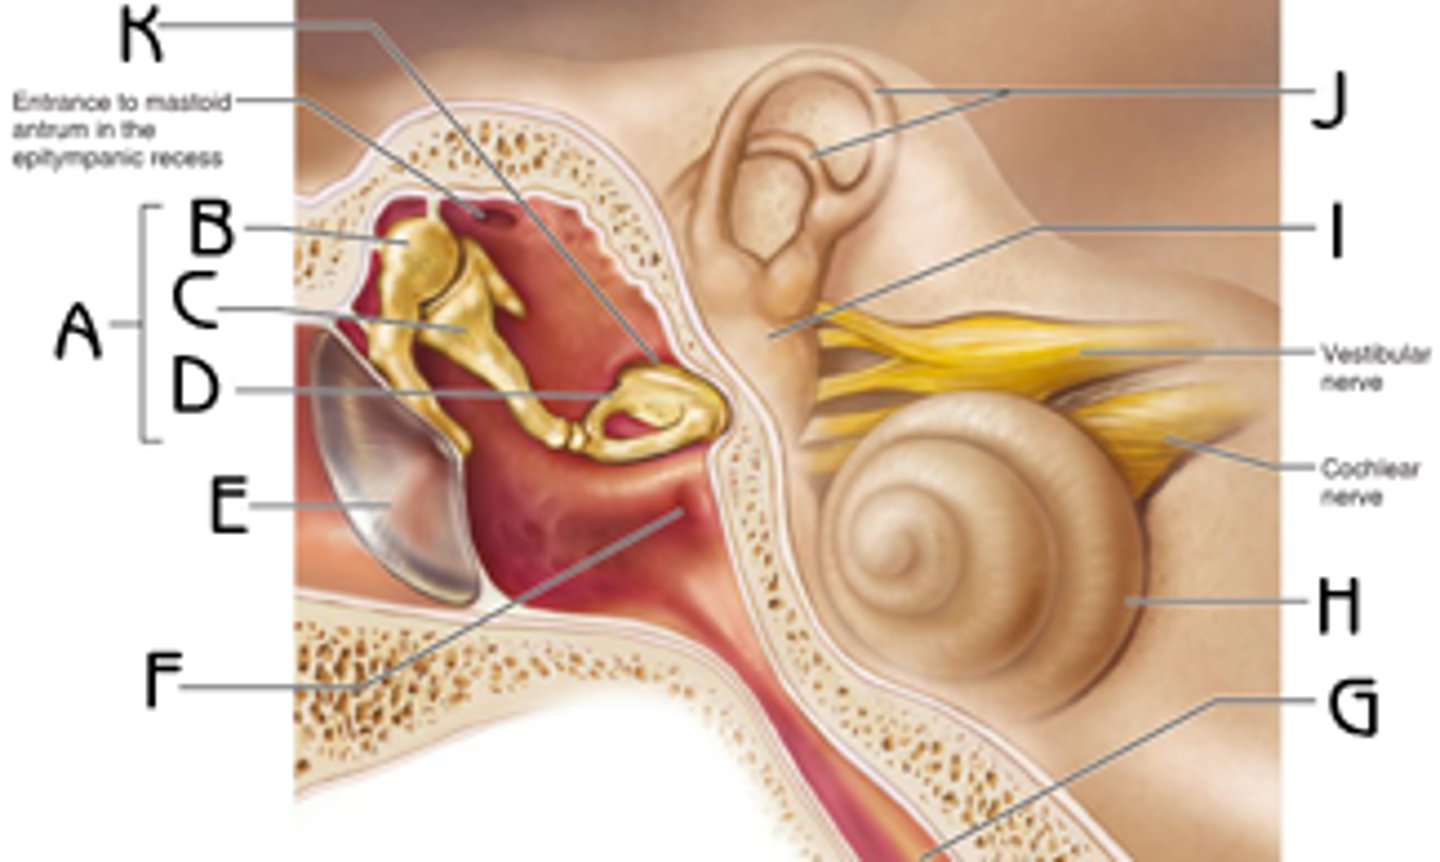

auditory ossicles

tympanic membrane

tympanic cavity

Eustachian tube

mastoid air cells

coclea

semicircular canals